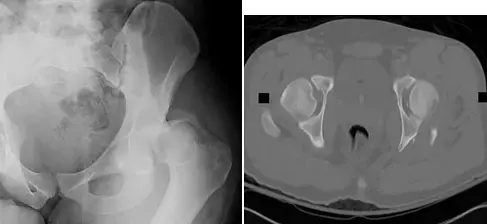

* الأشعة السينية (X-rays): لتحديد الكسور، التغيرات الهيكلية في العظام والمفاصل.

* التصوير المقطعي المحوسب (CT Scan): للحصول على صور ثلاثية الأبعاد للعظام، مفيد في التخطيط الجراحي للكسور المعقدة.